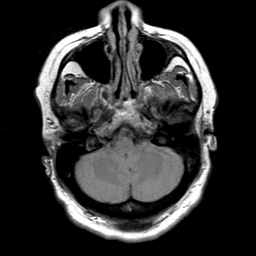

Cerebral hemorrhage, MR Study mr-pd -- Slice #5

[Home][Help][Clinical] Slice 5